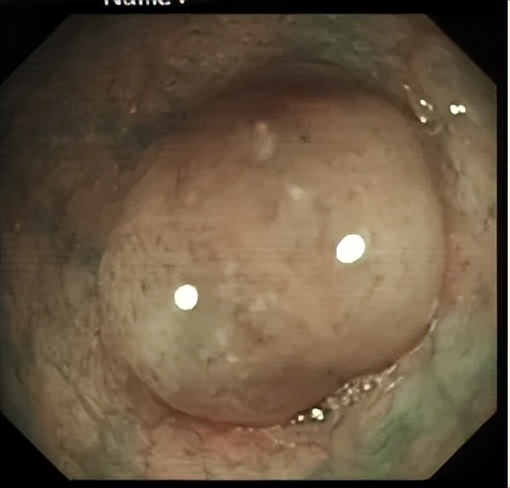

十年前,陳先生(化名)因常規(guī)體檢到羅湖區(qū)人民醫(yī)院消化內(nèi)科做結(jié)腸鏡檢查。檢查順利,但醫(yī)生在他的結(jié)腸里發(fā)現(xiàn)多個(gè)大小不一的息肉,有的像“小蘑菇”,有的是平坦隆起,其中直腸部位的息肉被確診為有明確癌變風(fēng)險(xiǎn)的絨毛狀腺瘤性息肉。

10年前直腸的另一枚息肉,同樣是需要處理的絨毛狀腺瘤性息肉。